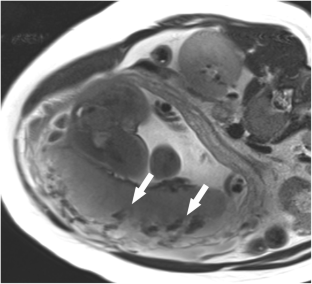

Fig. 1

Fig. 2

Fig. 3

Fig. 4

Fig. 5

Fig. 6

Fig. 7

Fig. 8

Fig. 9

Fig. 10

Fig. 11

Fig. 12